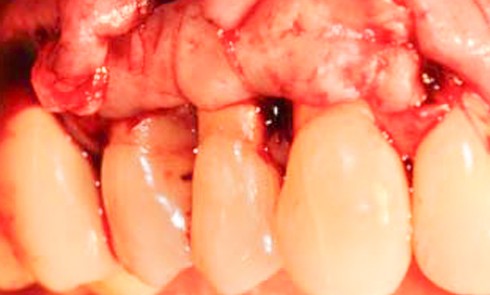

Après un examen clinique minutieux, le diagnostic de sourire gingival classe I de Parodontia lié à une éruption passive altérée de type I a été établi.

Le traitement classique est la gingivectomie associée à une ostéotomie. Cependant, plusieurs stratégies thérapeutiques étaient envisageables : intervenir sur l’arcade maxillaire complète, se focaliser sur le secteur antérieur ou bien intervenir uniquement sur les dents dont la hauteur coronaire était inférieure à la moyenne physiologique.

L’éruption passive altérée (EPA) est définie comme une anomalie du développement qui aboutit au recouvrement d’une partie des couronnes dentaires par la gencive. Ainsi, les dents ont une forme plus carrée…